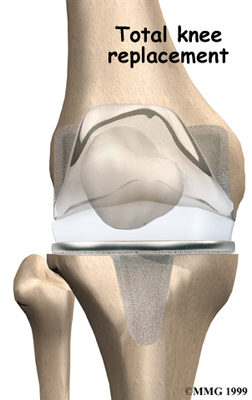

Artificial Knee Replacement

An artificial knee replacement is the ultimate solution for advanced knee OA.

Surgeons prefer not to put a new knee joint in patients younger than 60. This is because younger patients are generally more active and might put too much stress on the joint, causing it to loosen or even crack. A revision surgery to replace a damaged prosthesis is harder to do, has more possible complications, and is usually less successful than a first-time joint replacement surgery.

Related Document: FYZICAL Valley Stream's Guide to Artificial Joint Replacement of the Knee